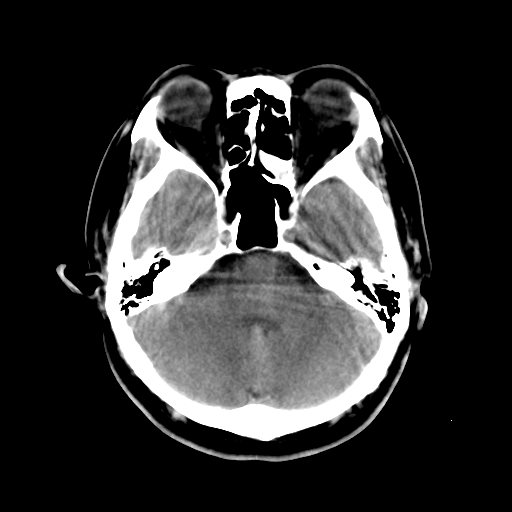

标题: CT15194:男,53岁,头痛、恶心三天。

男,53岁,头痛、恶心三天。

筛窦粘液囊肿。

筛窦粘液囊肿

筛窦囊肿、颅内未见明确异常

支持左侧筛窦后组粘液囊肿。